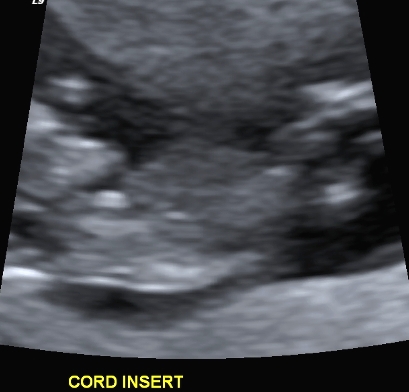

I finally managed to get hold of my u/s disc and have selected a few of the pics I think could have a nub in them (I'm still pretty hopeless at working out nubs).

There is only 1 pic from my 19 week scan that even comes remotely close to the bottom region and I'm pretty sure it is not a potty shot, just of legs from above I think??? (second last pic...biggest one)...I'm a little p'd off with the tech as I asked him to get a pic for me and he obviously didn't.